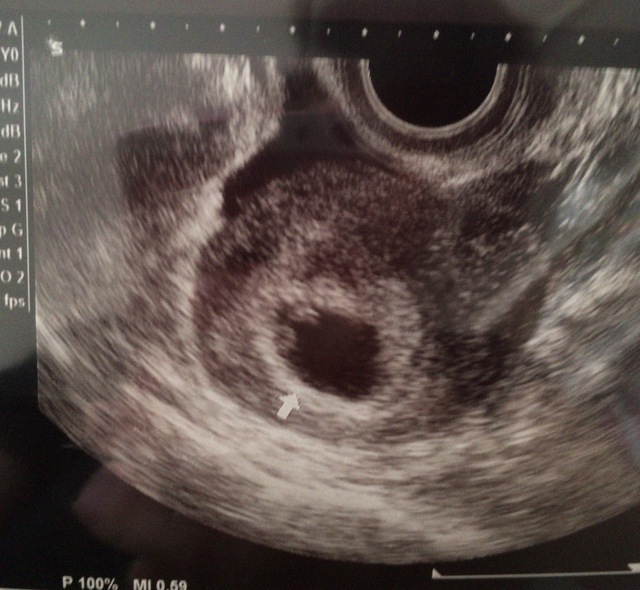

8週0日(8w0d・女の子)|akieeeen さん(26歳)

エコー写真撮影時のエピソード:

旦那が社員旅行に行っている時に送った写真です。検診に行ったらすぐに写真送ってって言われていたのですぐに送りました。

社員旅行中ですがエコー写真を見るなり電話してテンション上がっていたのを覚えています。電話ごしから赤ちゃんに声をかけていました。